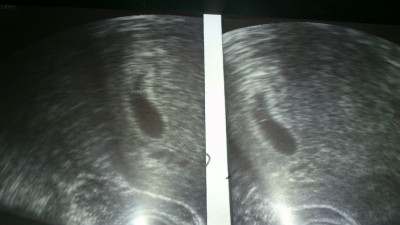

@happy familiy: Ich war heute früh zum zweiten Bluttest, also drei Tage nach dem ersten. Jetzt hoffe ich dass der Wert gestiegen ist. Habe sonst keinerlei Anzeichen, mir ist gar nicht übel oder so. Immer noch die Schmerzen und das Ziehen in der linken Seite aber der FA will mich frühestens nächste Woche sehen, wenn der Blutwert gestiegen ist. So richtig mit den Wochen komme ich nicht klar, bin heute bei PU+24, weiß aber nicht, was das in SS Wochen bedeutet. Ich habe immer noch große Angst, dass das Ziehen links eine Eileiter SS bedeutet oder Ähnliches zumal der Wert am Montag bei PU+21 mit 4160 auch sehr hoch war. Ich darf heute mittag anrufen und fragen...